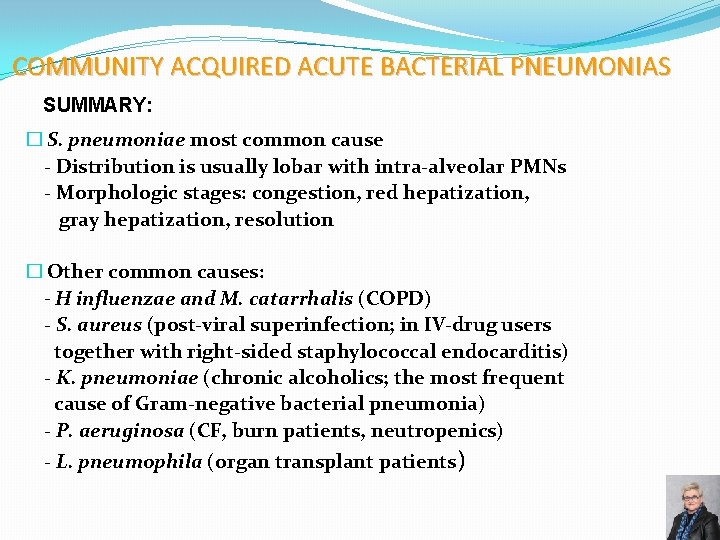

COMMUNITY ACQUIRED ACUTE BACTERIAL PNEUMONIAS SUMMARY: � S. pneumoniae most common cause - Distribution is usually lobar with intra-alveolar PMNs - Morphologic stages: congestion, red hepatization, gray hepatization, resolution � Other common causes: - H influenzae and M. catarrhalis (COPD) - S. aureus (post-viral superinfection; in IV-drug users together with right-sided staphylococcal endocarditis) - K. pneumoniae (chronic alcoholics; the most frequent cause of Gram-negative bacterial pneumonia) - P. aeruginosa (CF, burn patients, neutropenics) - L. pneumophila (organ transplant patients) 75